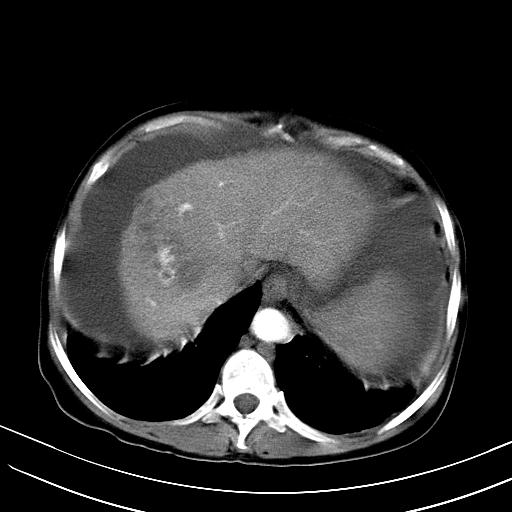

标题: CT23697:肝癌并肝动静脉漏? [打印本页]

标题: CT23697:肝癌并肝动静脉漏?

1)肝右叶肝癌并肝动静脉漏。2)肝硬化,腹水。3)胆囊炎。

肝右叶肝癌并动静脉漏,肝硬化,腹水。

1)肝右叶肝癌并肝动静脉漏 门v右支瘤栓伴海绵样变。2)肝硬化,脾大 腹水。3)胆囊炎。门v高压.

1)肝右叶肝癌并肝动静脉漏。2)肝硬化,腹水。3)胆囊炎。 4,脾大,脾囊肿

右叶肝癌并肝动静脉漏(动脉期肝动脉及门静脉内均可见造影剂),肝硬化,腹水。(胆囊壁水肿)

1)肝右叶肝癌,考虑并发肝动静脉漏。扫描时间好像慢了。2)肝硬化,门脉高压、脾大、腹水。